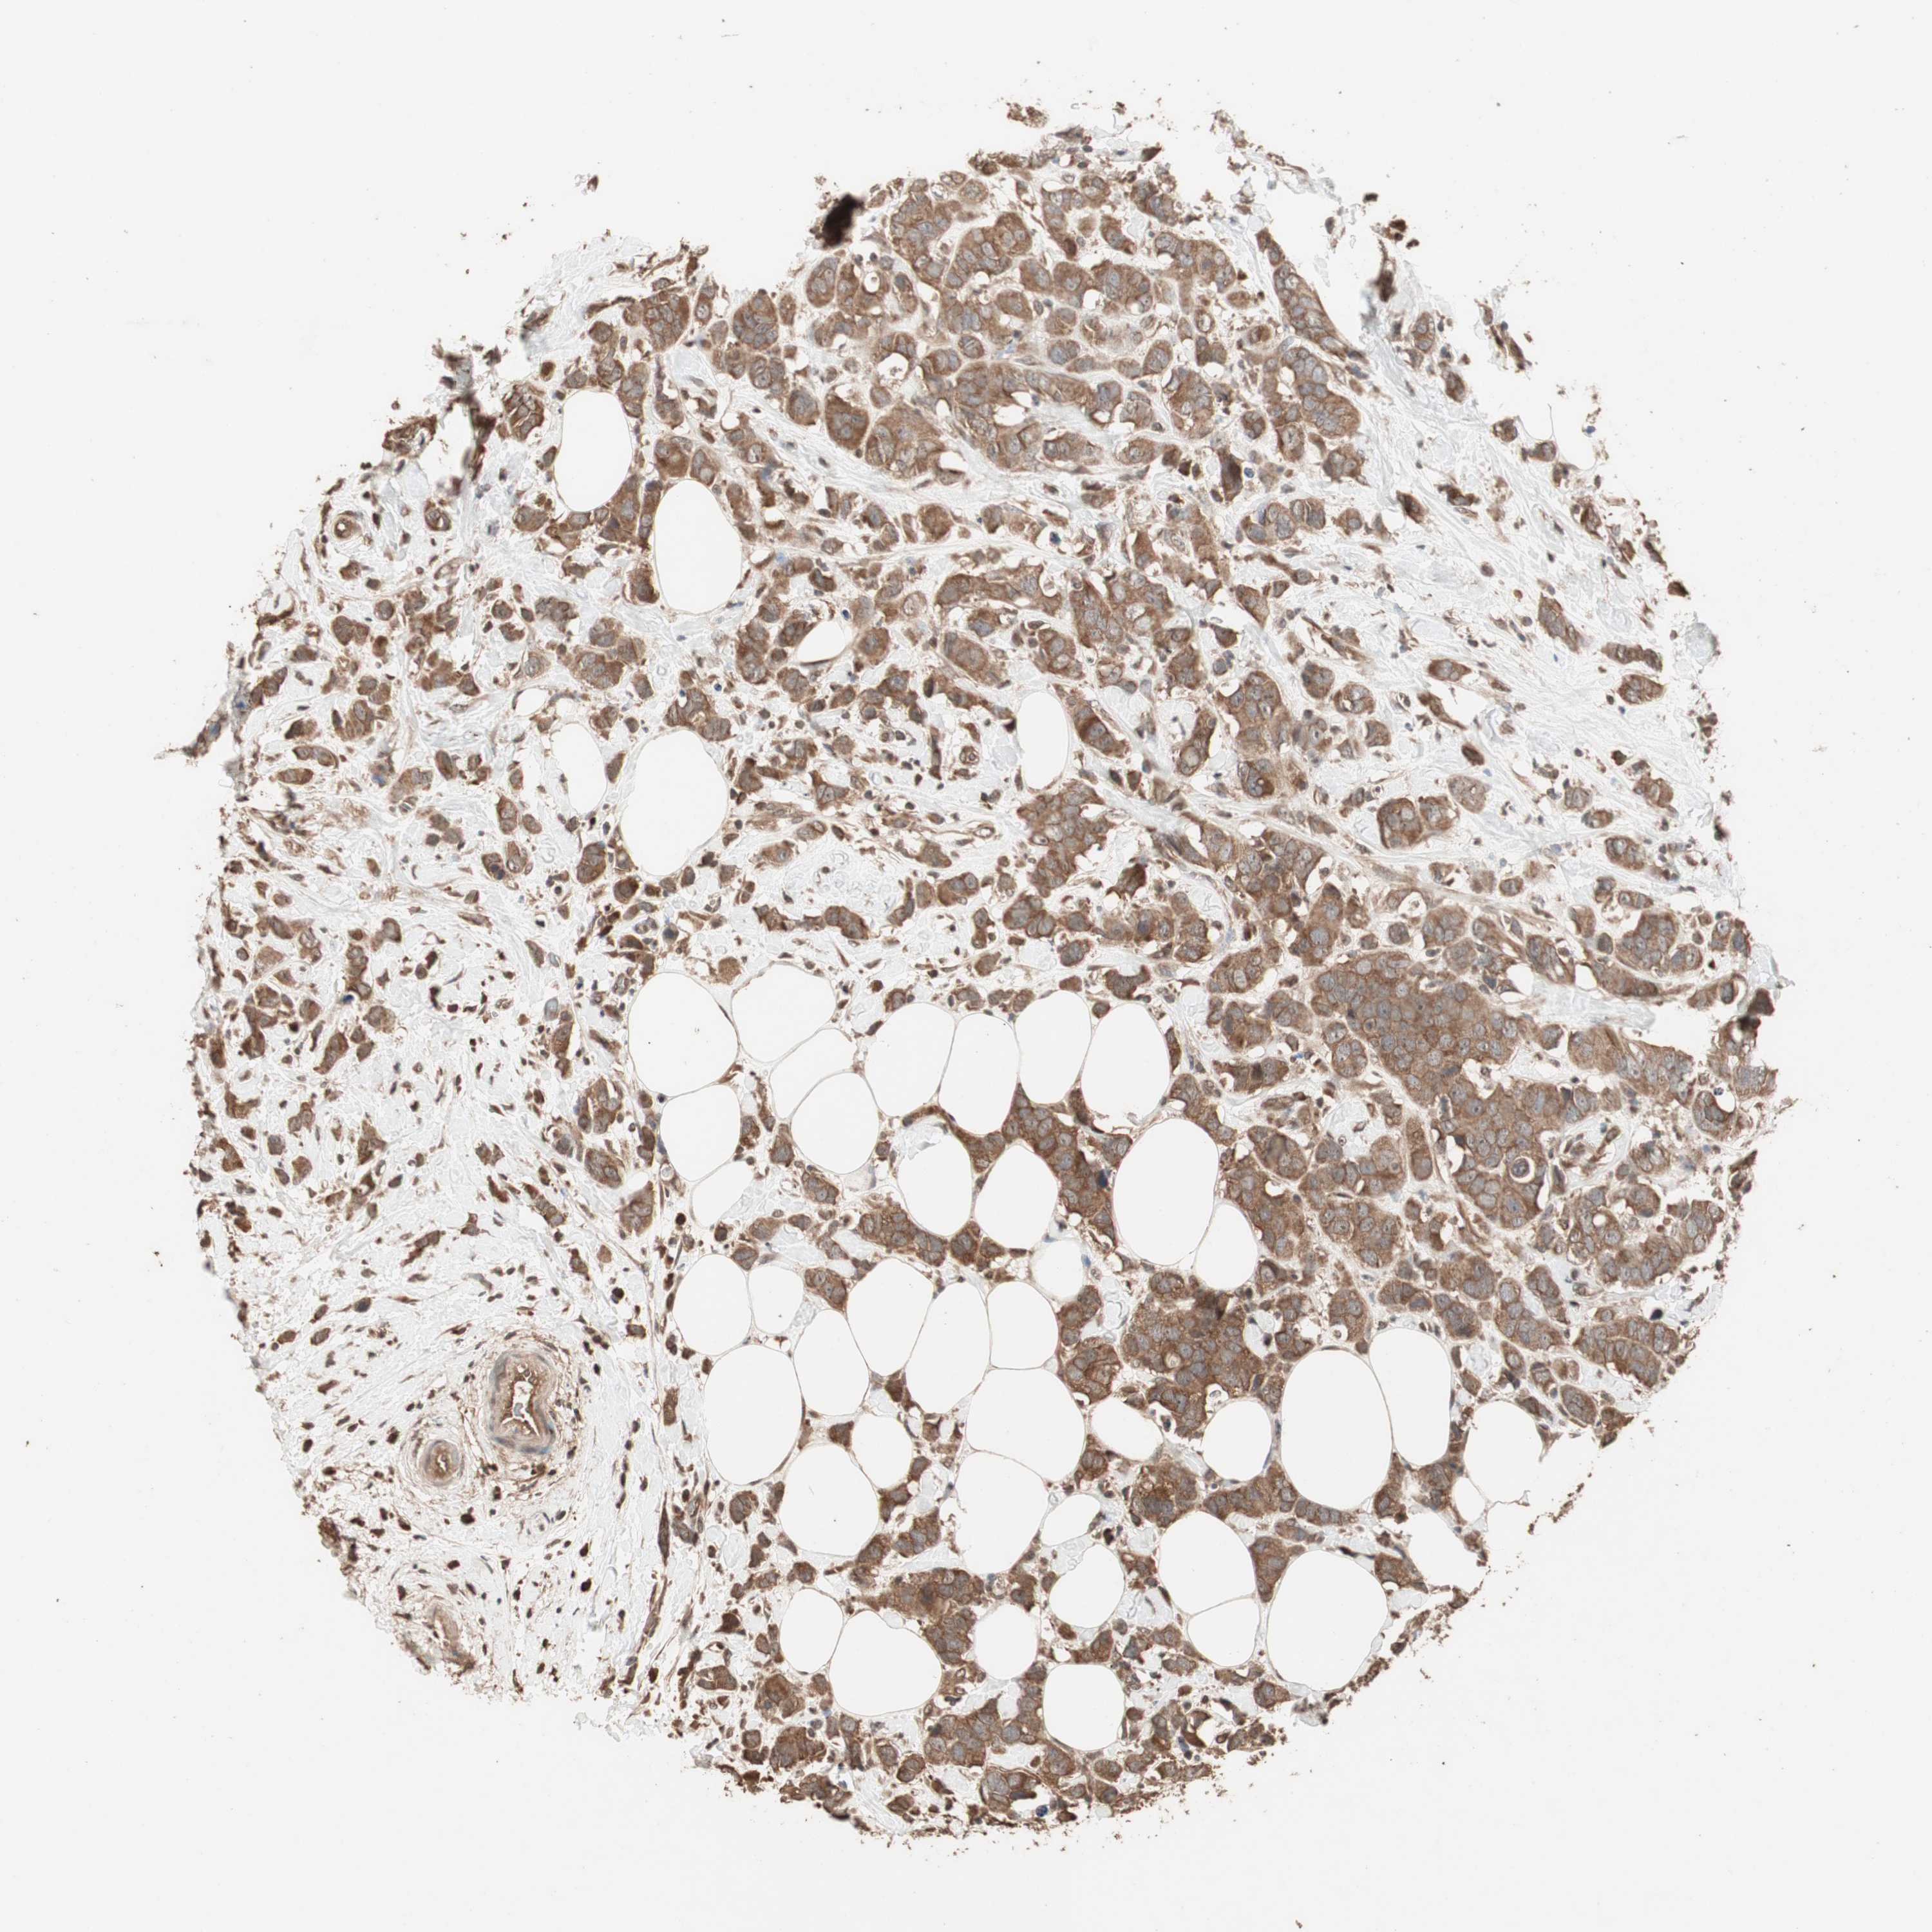

CANCER BREAST CANCER Show tissue menu

BRCA TCGA BRCA VALIDATION PROTEIN EXPRESSION